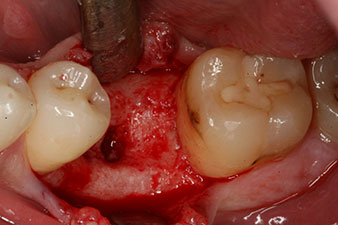

However, six weeks after the extraction incomplete ossification was found after preparation of the mucoperiosteal flap in the region of the former mesial alveolus.

The implant was placed as planned after thorough removal of the granulation tissue (blueSky, bredent).

The torque used for the machine-driven placement was 43 Ncm. In addition, after screwing a measuring post (SmartPeg) specially matched to the implant, the ISQ value was measured with the probe of the W&H Osstell ISQ module.

These values could have indicated open healing or even immediate restoration. Due to the insufficient crestal bone volume at the implant, the region was augmented with the bone chips collected during preparation of the implant bed and sutured to exclude saliva.